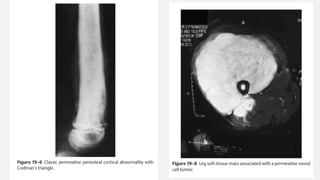

X-RAY IDENTIFICATION

• Destructive lesion in the diaphysis of a long bone

• “Onion skin” periosteal reaction

(In reality, Ewing sarcoma more often originates in the metaphysis of a long

bone but frequently extends for a considerable distance into the diaphysis)

• Typical “triad’’ of findings on imaging:,

• (1) a “diaphyseal’’ location,

• (2) a “round-cell’’ or “permeative’’ appearance

• (3) an obvious or large soft-tissue mass associated with the tumor

• Periosteal Reaction – Codman’s Triangle, Sunburst Appearance can be seen

EWING’S SARCOMA FEMUR

• An otherwise healthy 20-year-old male developed a sudden increasing pain in his right

femur. The pain is so severe that he is unable to walk, needs crutches, and requires

high doses of narcotics. The pain awakes him from sleep. There is no history of

associated trauma. He has not noticed any pal- pable mass nor antecedent pain in his

right femur. Of note, he had a prior anterior cruciate ligament reconstruction on his

right side, but this procedure was done in the distant past and is unrelated to any of

his pain. He has actually had excellent rehabilitation from that procedure and tolerated

the procedure well. He has had no associated fever or chills. White count and

infectious laboratory work reveal normal sedimentation rate and C-reactive protein

(CRP). Anteropos- terior and lateral femur (Fig. 19–1 and Fig. 19–2) films show a lytic

lesion of the middiaphyseal region with a sun burst periosteal reaction. Magnetic

resonance imaging (MRI) (Fig. 19–3 and Fig. 19–4) revealed a soft tissue mass with a

right peritumoral inflammatory zone associated with it. The mass measures

approximately 5 × 4 × 3 cm. Computed tomogra- phy (CT) scan shows cortical

erosions as well. A chest CT also was performed, showing no obvious pulmonary

metastases. A bone scan was ordered as well (Fig. 19–5).

Orthopedic Oncology by Ernest Conrad

Thieme